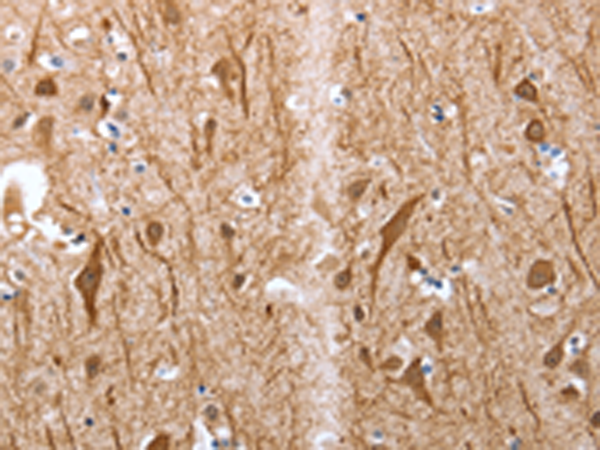

分类: 科研抗体货号: P11132别名: MAP-2; Mtap2; Mtap-2应用: IHC反应种属: Human, Mouse, Rat